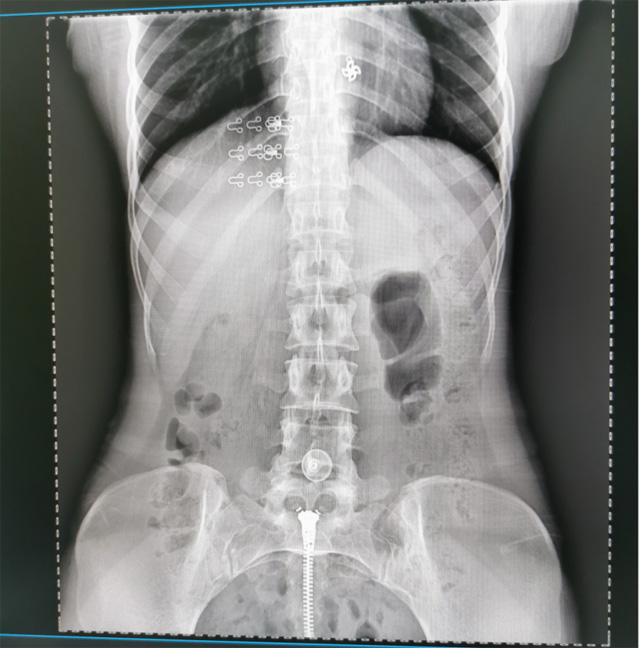

提高醫(yī)院的影像科的醫(yī)療服務(wù)水平,滿足滿足人民群眾不斷增長的醫(yī)療需求,促進醫(yī)療技術(shù)快速發(fā)展。醫(yī)院都引進懸吊DR拍片設(shè)備新一代數(shù)字化X線攝影系統(tǒng)。標(biāo)志著醫(yī)院的診療水平又上升一個新的臺階。懸吊DR滿足人體頭部、胸部、腹部、腰椎、四肢等部位的數(shù)字?jǐn)z影檢查,可以檢查呼吸系統(tǒng)疾病,心臟系統(tǒng)的疾病、骨關(guān)節(jié)系統(tǒng)的疾病,子宮輸卵管造影、胃腸道造影,.有職業(yè)病體檢篩查塵肺病功能。通過DR數(shù)字化攝影,分段連續(xù)、重疊采集數(shù)字化圖像,利用軟件對圖像進行拼接的方式來獲得全脊柱、全上肢或全下肢的圖像。新設(shè)備的圖像更清晰,臨床拍攝避免患者再次搬運和移動產(chǎn)生的痛苦,是創(chuàng)傷骨折患者的福音。輻射減少受照劑量50%,后處理能力強、圖像質(zhì)量高。有效降低操作難度,縮短工作流程,尤其適合大批量體檢。

具有射線劑量小、圖像清晰度高、誤差小等特點,懸吊DR已廣泛應(yīng)用于各級醫(yī)療機構(gòu)的體檢中心,越來越受到臨床醫(yī)生的肯定和患者的青睞。為臨床診斷工作提供更加直觀有效的技術(shù)支持,大大提高了患者就醫(yī)效率從而為患者提供更加優(yōu)質(zhì)的醫(yī)療服務(wù)。提高了其成像質(zhì)量和臨床應(yīng)用價值,并極大減少了受照輻射劑量。有效滿足了各種常見疾病的臨床診斷和治療需求。以醫(yī)療質(zhì)量為根本,以優(yōu)質(zhì)服務(wù)為導(dǎo)向,竭誠為人民群眾的健康保駕護航。